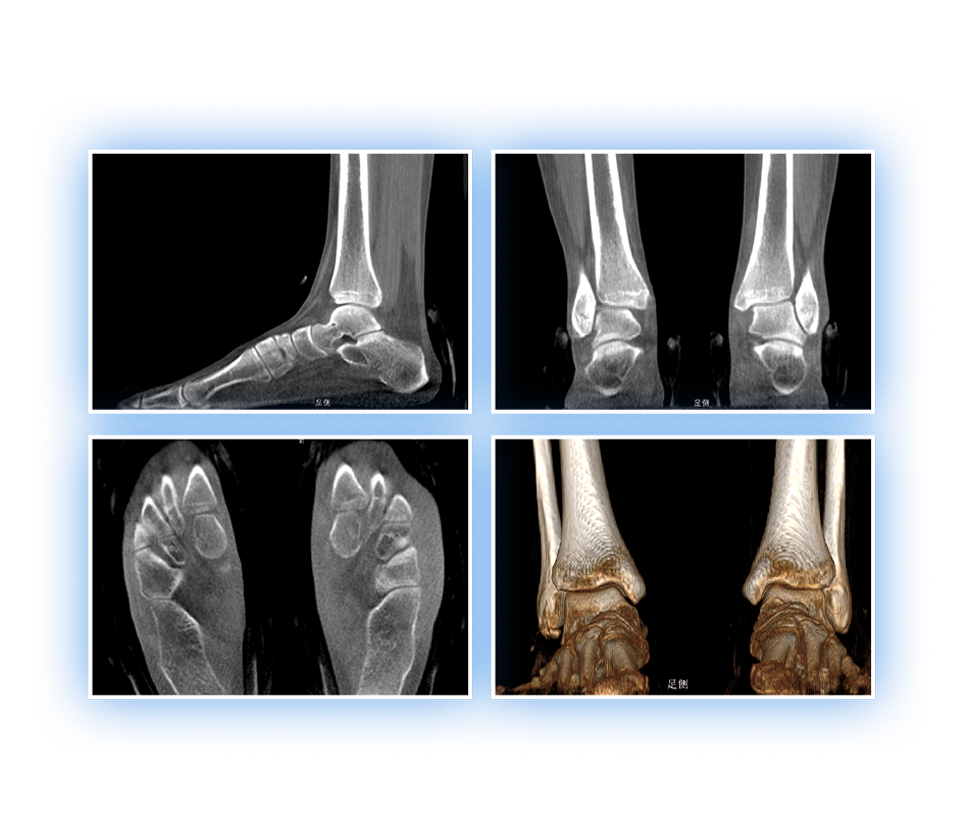

• 足踝

2D+3D一站式快速检查

支持双腿或双侧髋关节扫描 | 方便对比,降低漏诊误诊